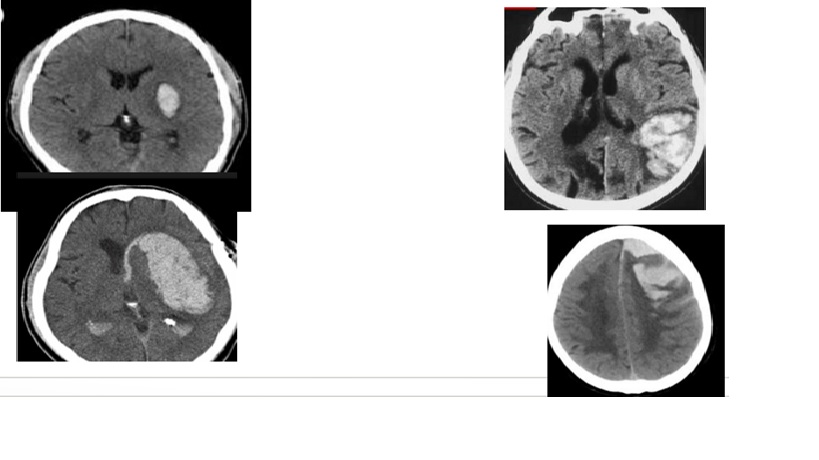

Deep hypertensive hemorrhage vs Lobar (amyloid ) hemorrhage

ICH from a bleeding Tumor